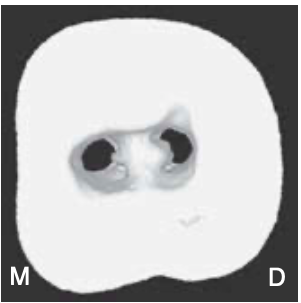

type IV of pulpal floors

non–C-shaped floors

one distal canal orifice and one oval or two round mesial canal orifices are present (least common)